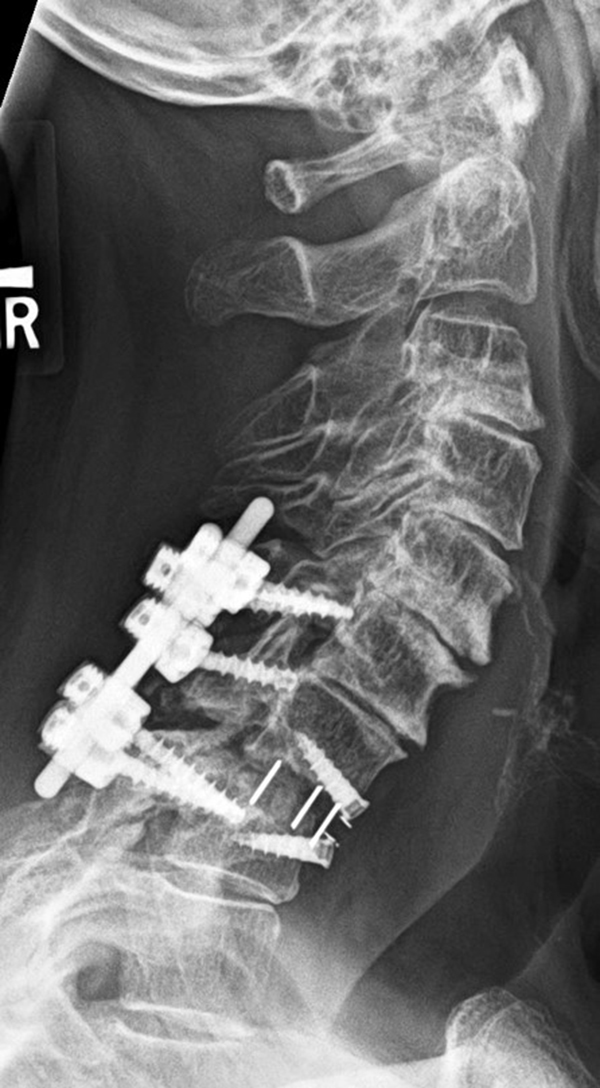

Young woman with traumatic locked facets at C6-7 and C7 body fracture. A posterior cervical fusion with lateral mass screws (cervical spine) and pedicle screws (thoracic spine) and rods extends from C4 to T2. There is an anterior cervical fusion plate and screws at C6-7 with a intervertebral disk cage at C6-7 and a crosslink at C6. |